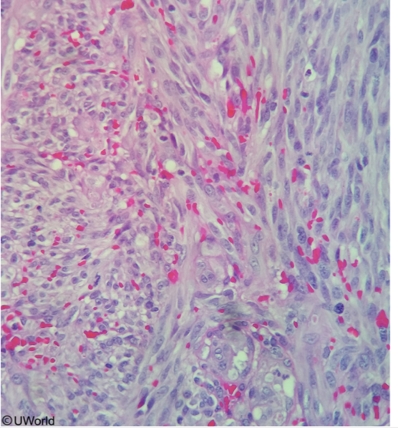

This patient's myocardial biopsy shows interstitial fibrosis with central lymphocytes and macrophages as well as scattered multinucleated giant cells (green arrow). This interstitial myocardial granuloma, or Aschoff body(encircled), is pathognomonic for ARF-related myocarditis. Plump macrophages with abundant cytoplasm and central, slender chromatin ribbons called Anitschkow (or caterpillar) cells are also often present. Over subsequent years, Aschoff bodies are replaced by fibrous scar tissue, leading to chronic mitral valve stenosis and regurgitation.